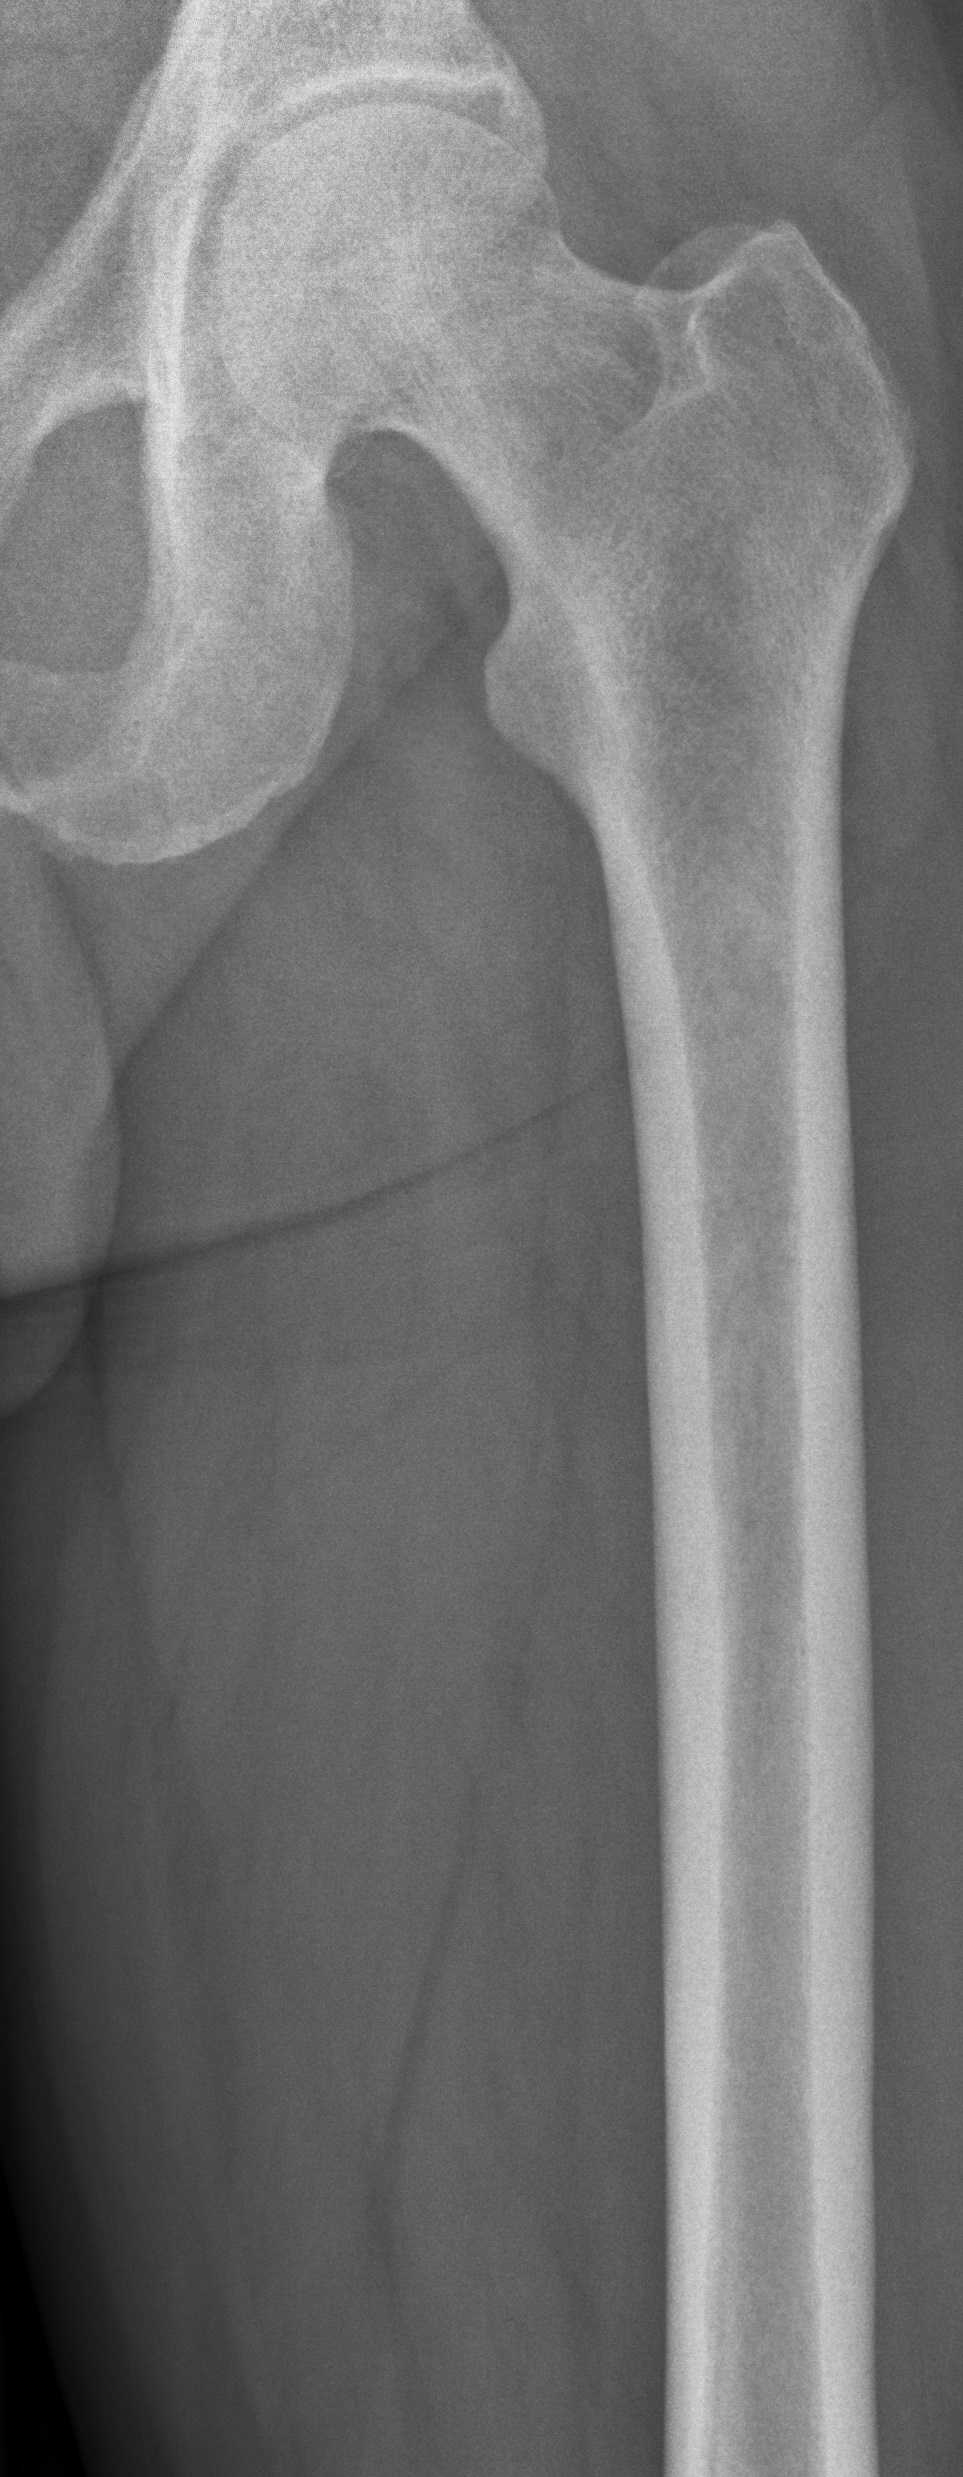

Radiograph of a left femur used as a reference baseline for orthopaedic imaging.